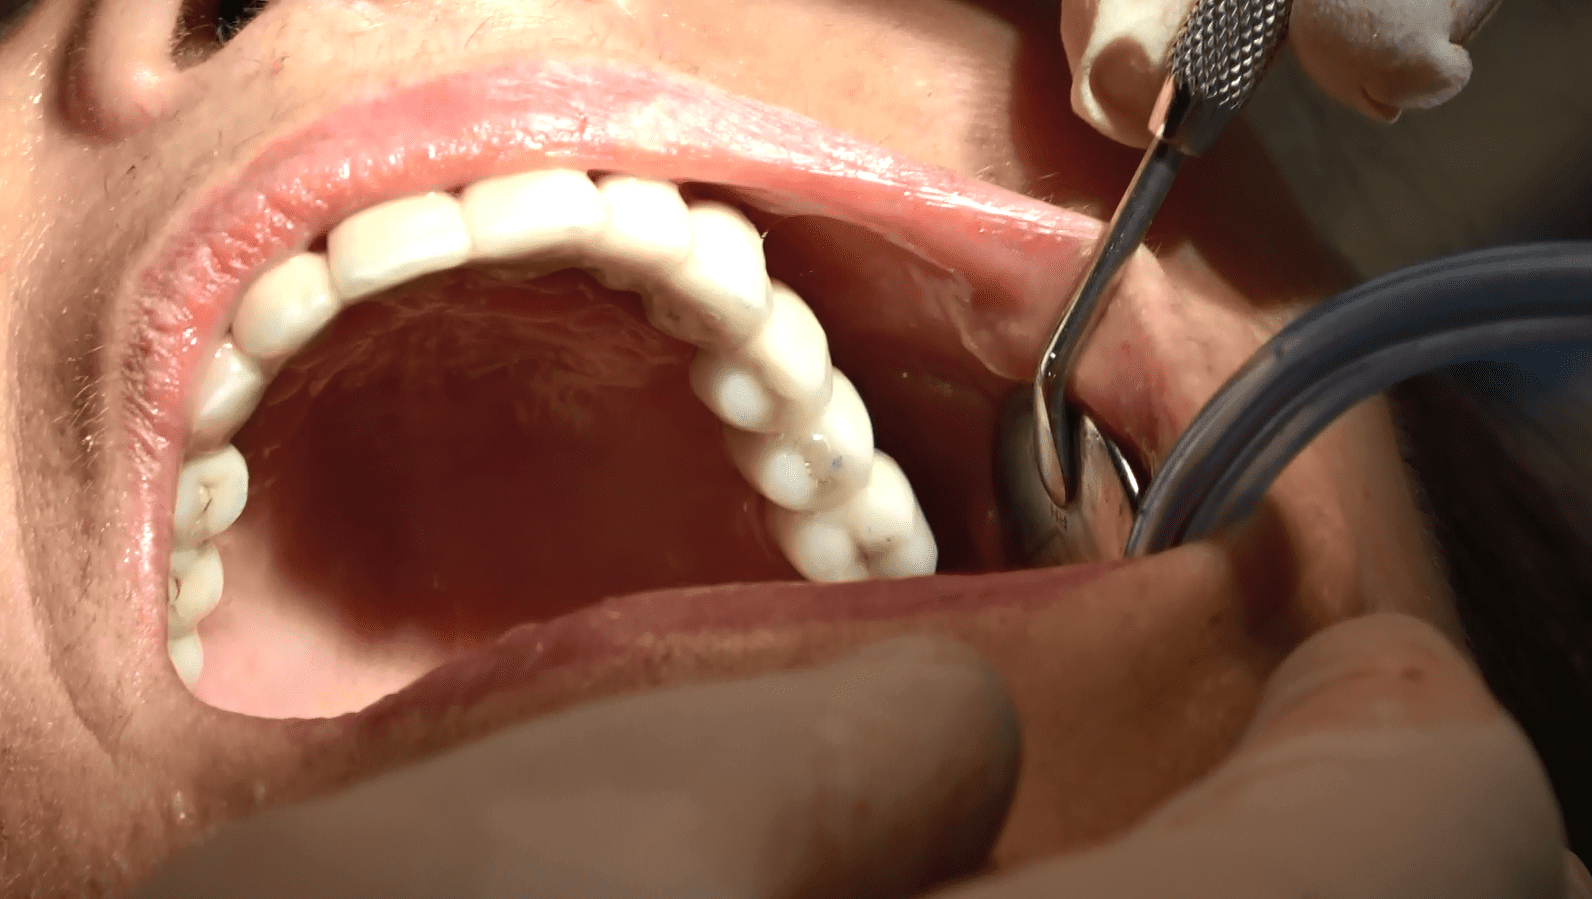

Risultati e Prospettive:

Il paziente, dopo un periodo di recupero relativamente breve, ha ripristinato la funzionalità e l’estetica del sorriso. Questo caso dimostra come l’implantologia sottoperiostea possa essere una soluzione efficace anche per pazienti con atrofia ossea estrema, offrendo risultati duraturi e soddisfacenti.